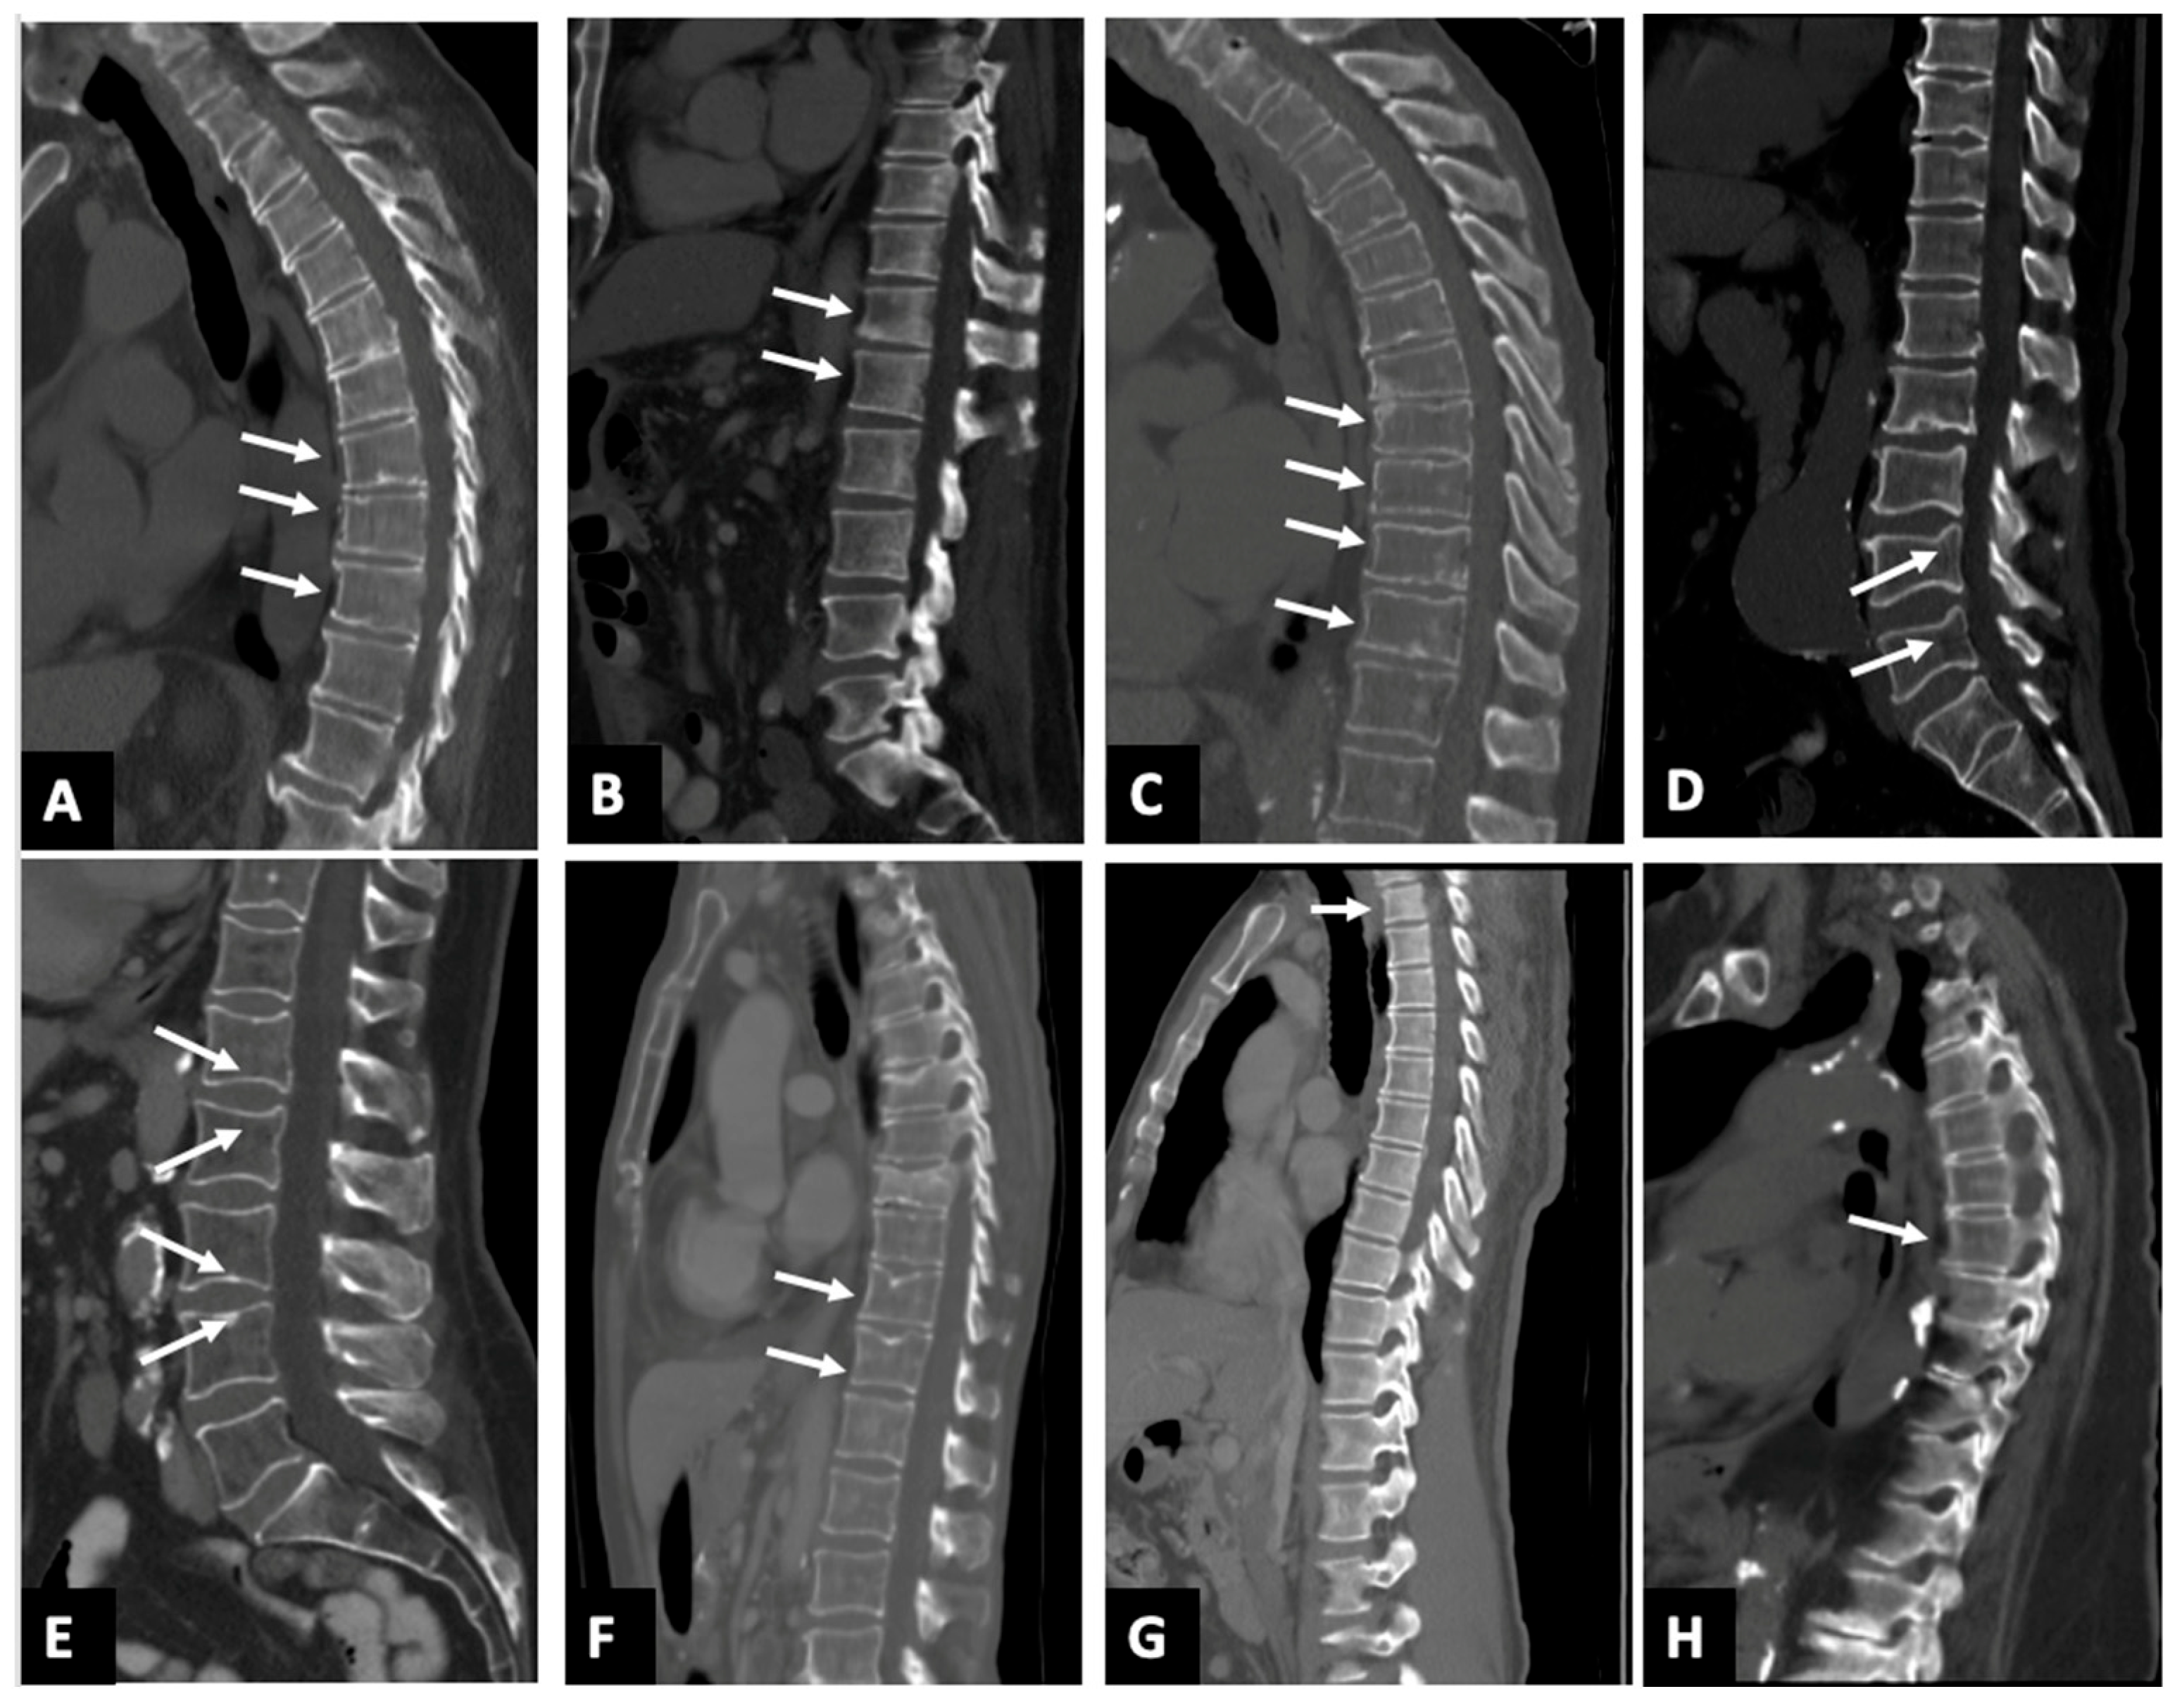

3.3. False Positives

3.4. Detection of Missed Fractures